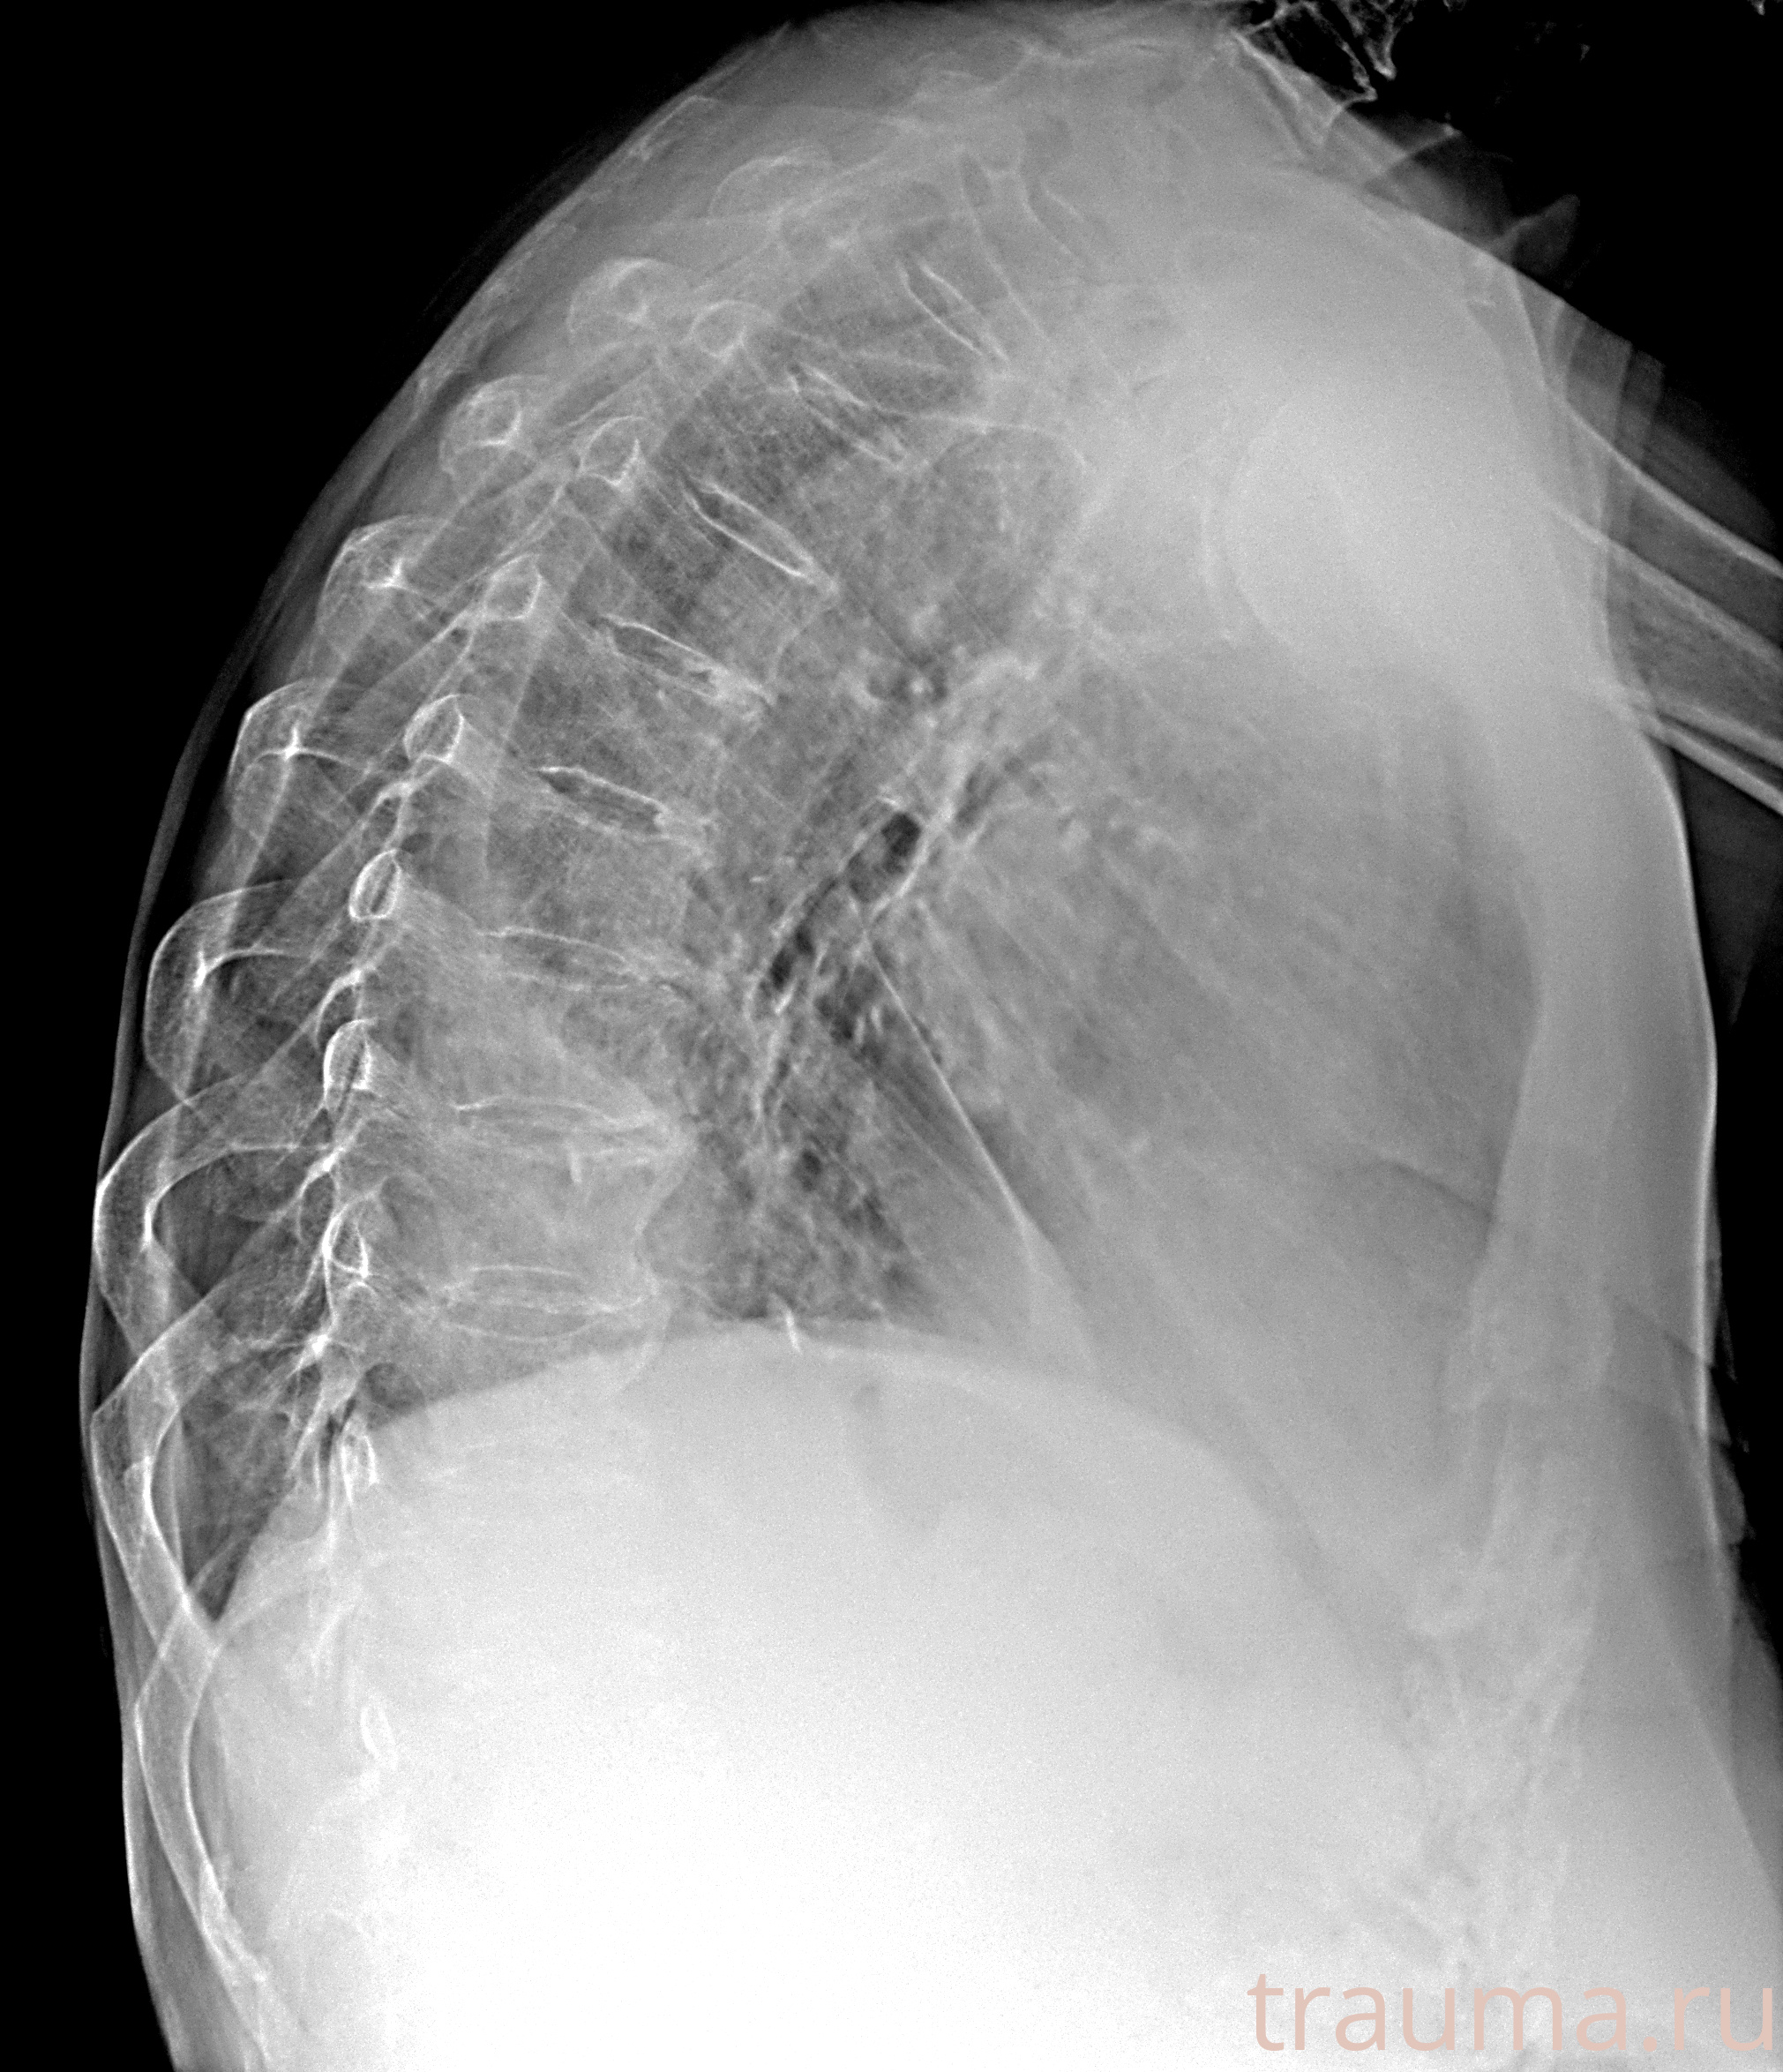

Рентгенограммы

Рентген на дому: по вашему адресу приезжает врач-рентгенолог, травматолог-ортопед с мобильным рентгеновским аппаратом, проводит диагностику травмы или заболевания, делает необходимые рентгенограммы, дает рекомендации по дальнейшему лечению. Получить качественные снимки в домашних условиях возможно благодаря уникальной методике, разработанной МосРентген Центром для института  Склифосовского

Яркость: 1   Контраст: 1   Инвертировать: 0 Увеличение: 1

Перетаскивайте мышь вверх/вниз для контраста, влево/право для яркости. Прокрутка колесом изменяет масштаб. Нажмите Сбросить для возврата к исходному изображению. При увеличении держите мышь в той области, которую хотите рассмотреть.